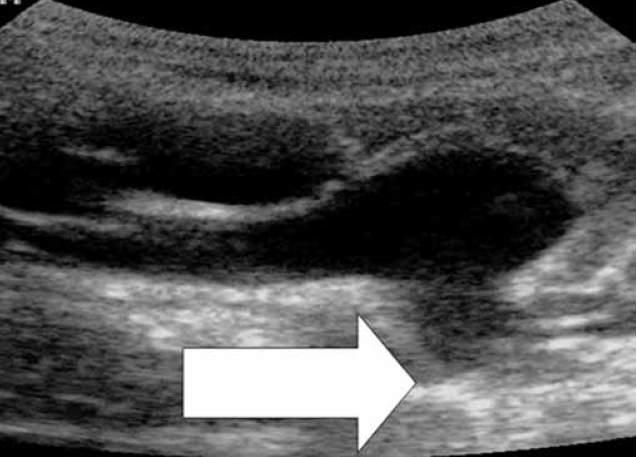

В ходе работы был выявлен важный эхокардиографический диагностический признак. При ЭХО КГ сердца из левой парастернальной позиции по короткой оси на уровне ствола легочной артерии у 51 % детей с диагностированным ОАП имелся «дефицит» ткани аортолегочной связки (ligamentum arteriosum), визуализируемой в поперечном сечении непосредственно под бифуркацией ствола легочной артерии, а у 8 % детей ткань связки вовсе не визуализировалась (рис. 7).

Рис. 7. Визуализация аортолегочной связки (ligamentum arteriosum) в области бифуркации ствола легочной артерии (отмечено стрелкой). Дефицит или отсутствие ткани может указывать на наличие открытого артериального протока

- При визуализации бифуркации легочной артерии из левого парастернального доступа по короткой оси дефицит или полное отсутствие ткани в проекции аортолегочной связки (ligamentum arteriosum) может свидетельствовать о наличии ВПС ОАП.